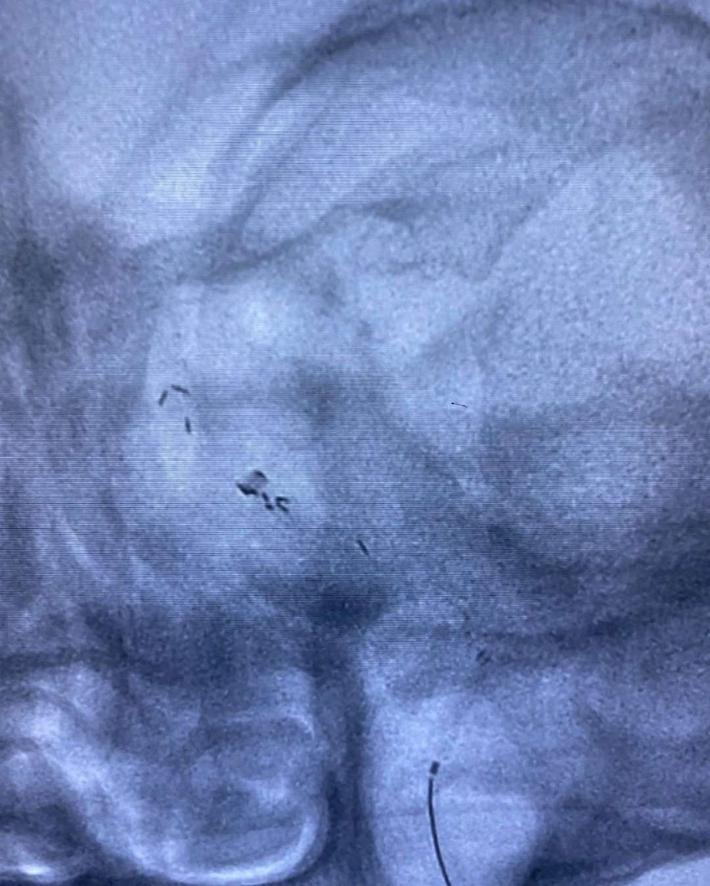

2020.07.10晚,患者术后第4天逐渐出现意识迷糊,嗜睡,考虑支架闭塞可能。遂急诊造影示:支架内血栓闭塞,意识模糊,危在旦夕,外院兄弟果断尝试再通,导丝导管通过后血流线样再通,撤回微导管注射替罗非班,血流难以维持。

再次尝试通过导丝导管,支架移位变形严重。

经过尝试,支架导管Rebar 18➕Synchro导丝200cm通过变形严重的原支架Enterprise 2。

打开取栓支架。

Solitaire AB 4mmx20mm成功挂住Enterprise 2。

尝试回收支架至5F Navien,牵扯力量比较大,提心吊胆。

经反复收拉尝试,最终取出Enterprise 2支架。

Enterprise 2支架在血管内两端严重变形,反折的Mark恰好被Solitaire AB支架咬合取出。